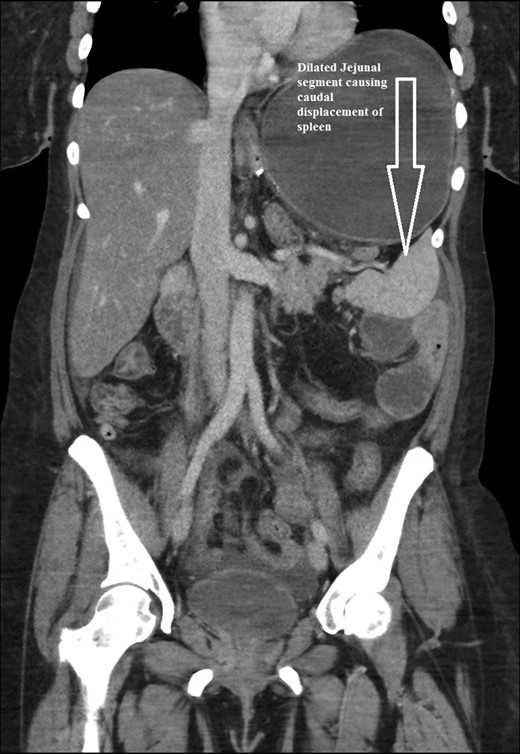

The intraoperative findings were not consistent with the radiological findings (Figs 1–4). As shown in the CT scan of abdomen and pelvis; multiple loops of dilated small bowel were seen, more predominantly dilated and matted bowel complex just above the spleen. The dilated bowel complex was decompressed using needle aspiration to help reduction of the bowel loops. The ileo cecal junction was then identified and traced back to the perisplenic hilar region. The trifurcation of three bowel loops (Roux limb, biliopancreatic limb and common limb) were identified with identification of ligament of Treitz. The prior gastric bypass was of ante colic- ante gastric type and Peterson’s defect was not closed. The above described bowel trifurcation had sunken postero- inferior to the spleen and had herniated through a potential space underneath the spleen and torsed around the splenic vessels and hilum. This picture was consistent with perisplenic small bowel volvulus. As noted earlier there was a massively dilated proximal small bowel segment above the spleen, displacing it caudally. Careful adhesiolysis was performed inferior to the spleen to release the segment of the trifurcation. The bowel segments once reduced were assessed and appeared viable. Of note, the spleen appeared better perfused after reduction. The remnant hernia defect of size 2 × 3 × 2.5 cm around the hilar region was then approximated using interrupted non-absorbable sutures. Enterotomy at the decompression site was closed with non absorbable suture. All potential sites of IH were re-examined and there was no evidence of any other internal herniation. Coelomic cavity was thoroughly irrigated and operation concluded successfully. Postoperative hospital stay was uneventful, and the patient was discharged home after two days.

Coronal CT scan of abdomen and pelvis showing Dilated jejunal segment causing caudad splenic displacement.